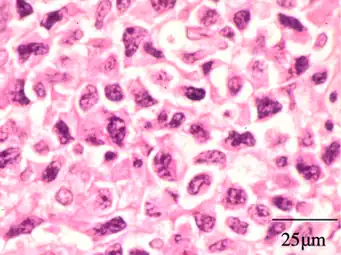

Histopathology of sinonasal contents removed from surgery can be diagnostically valuable:

-

Benign chronic mixed inflammation of an inflammatory sinonasal polyp -

Acute inflammation characterized by neutrophils -

Extranodal NK/T cell lymphoma, nasal type.[105] It may be incidentally discovered in people undergoing surgery for sinusitis.[106]